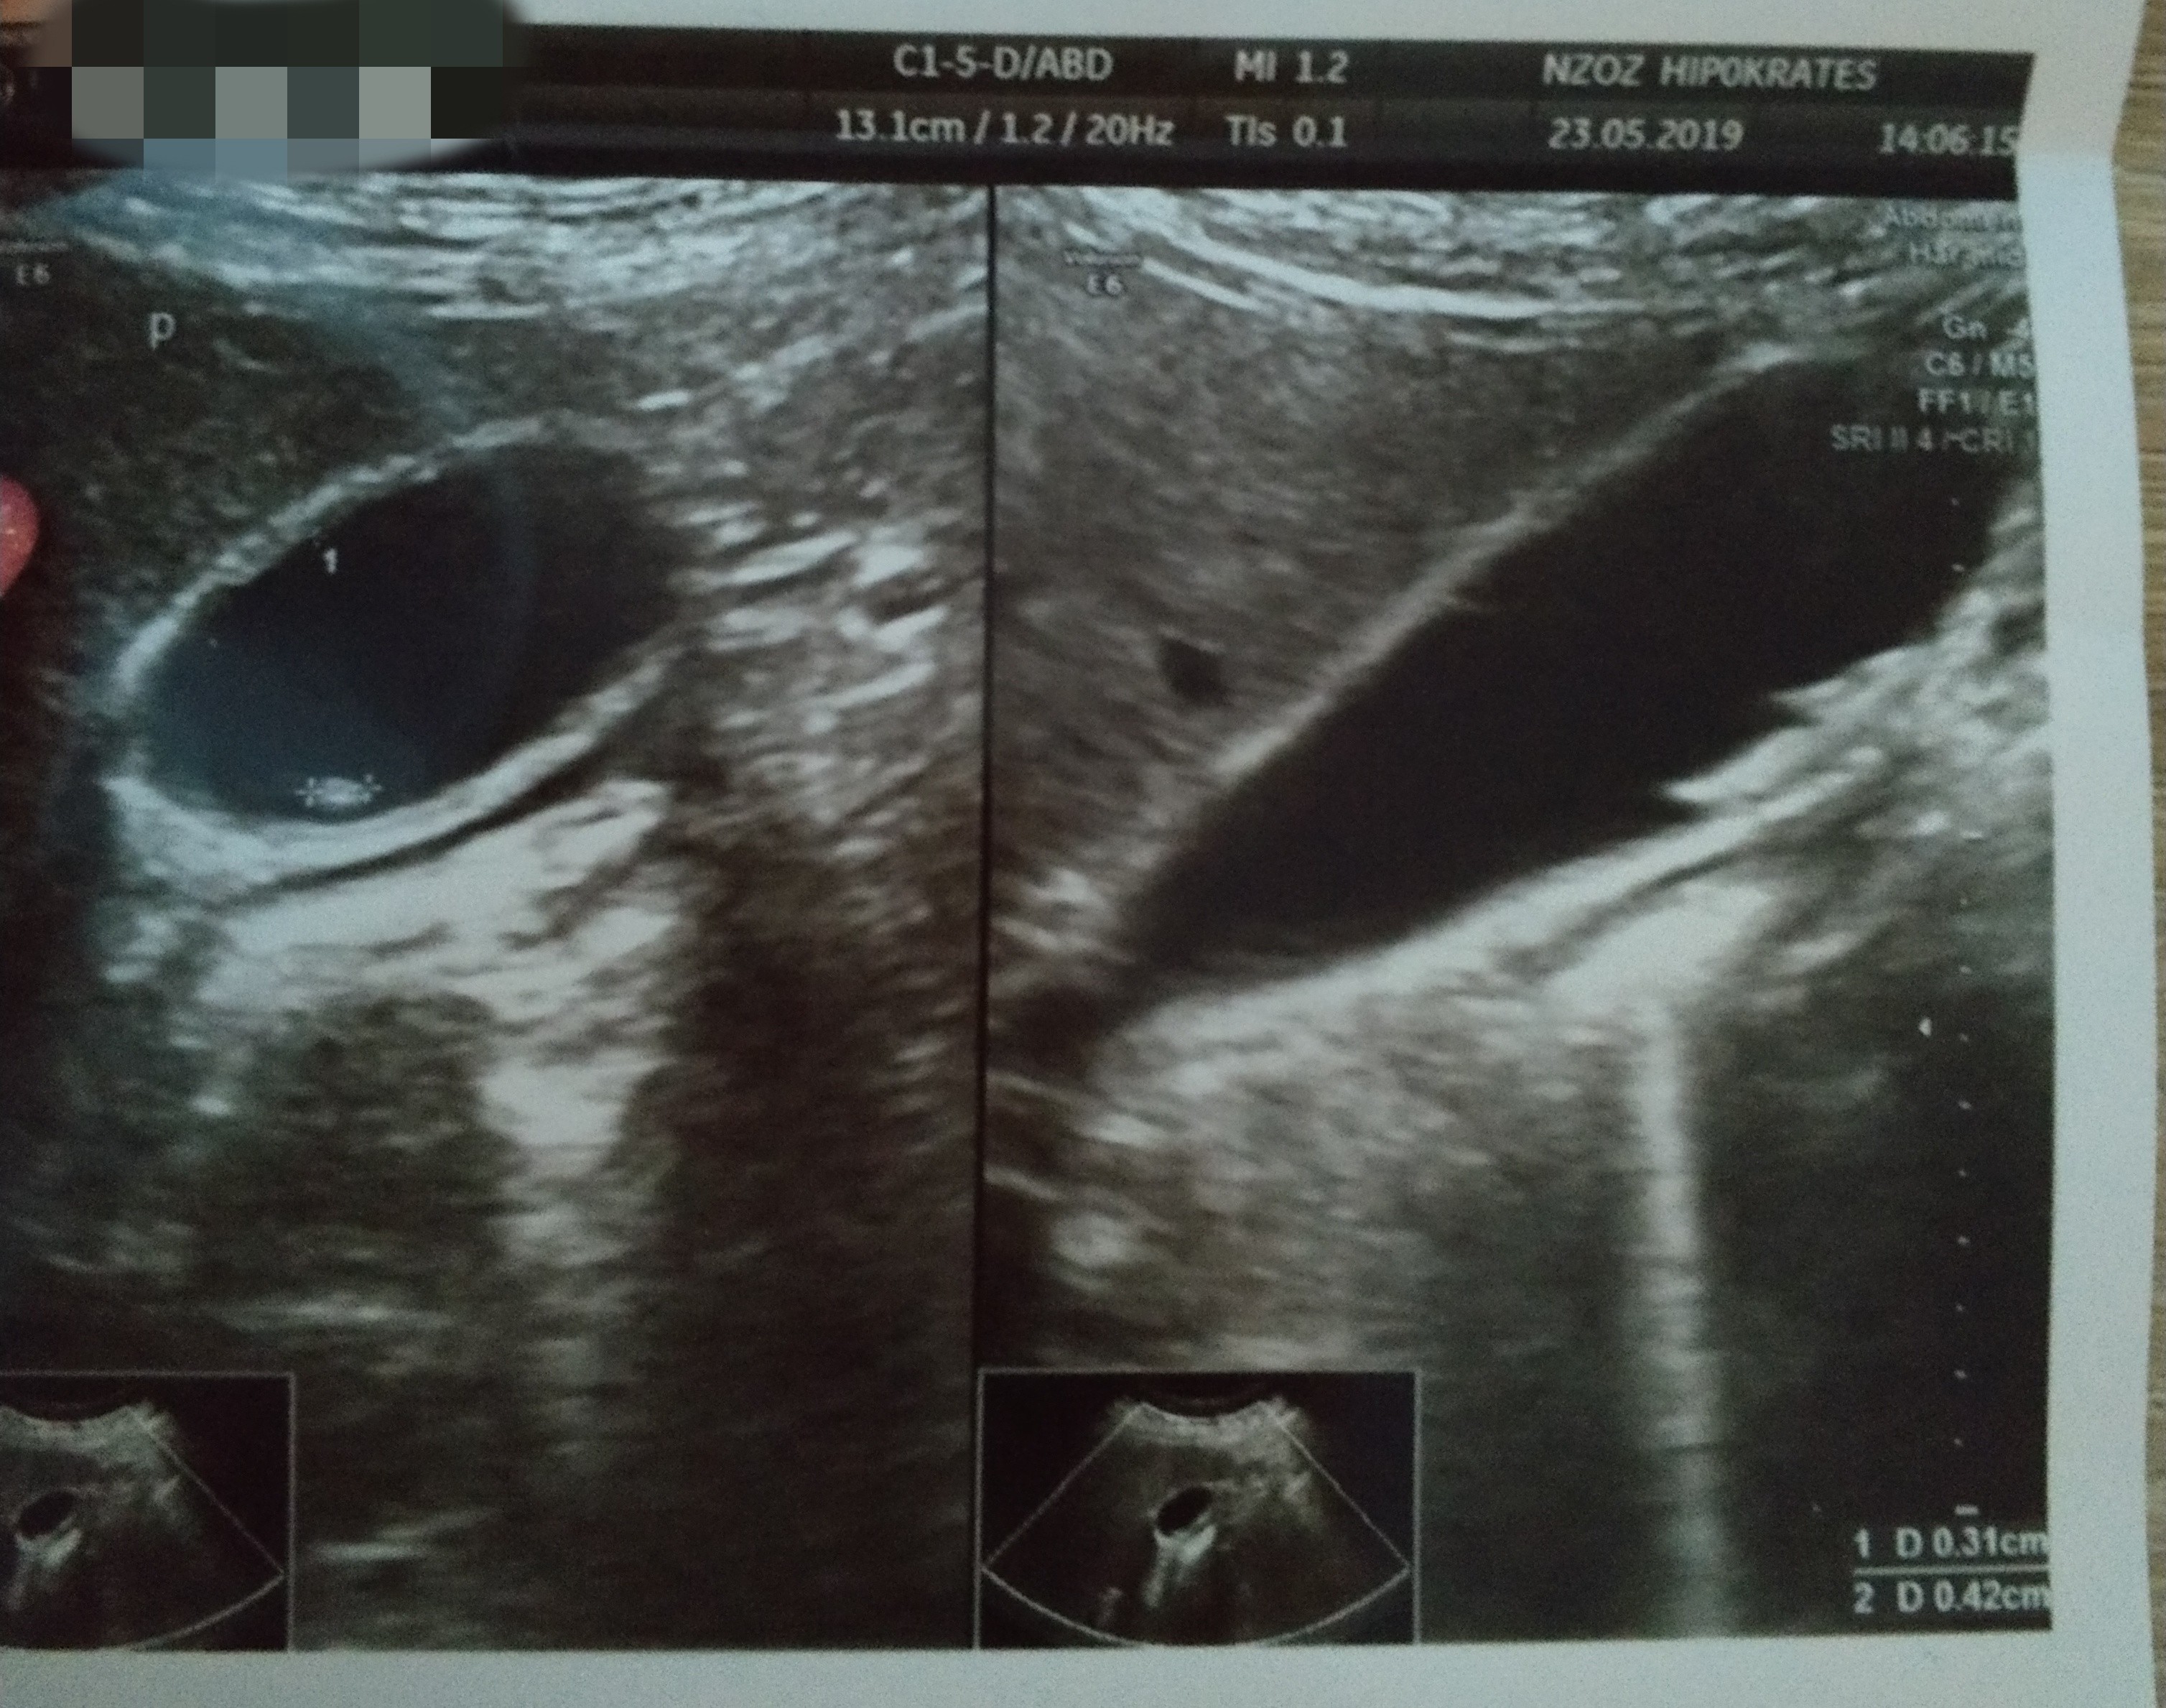

Jestem dzis po Usg brzucha. I juz nie musze isc na gastroskopie. Mam diagnoze. Bardzo liczne kamienie w woreczku zolciowym o wielkosci od 4 do 10mm.

Przedstawiam wam moich niechcianych lokatorów..

IMG_20190523_210736.jpg